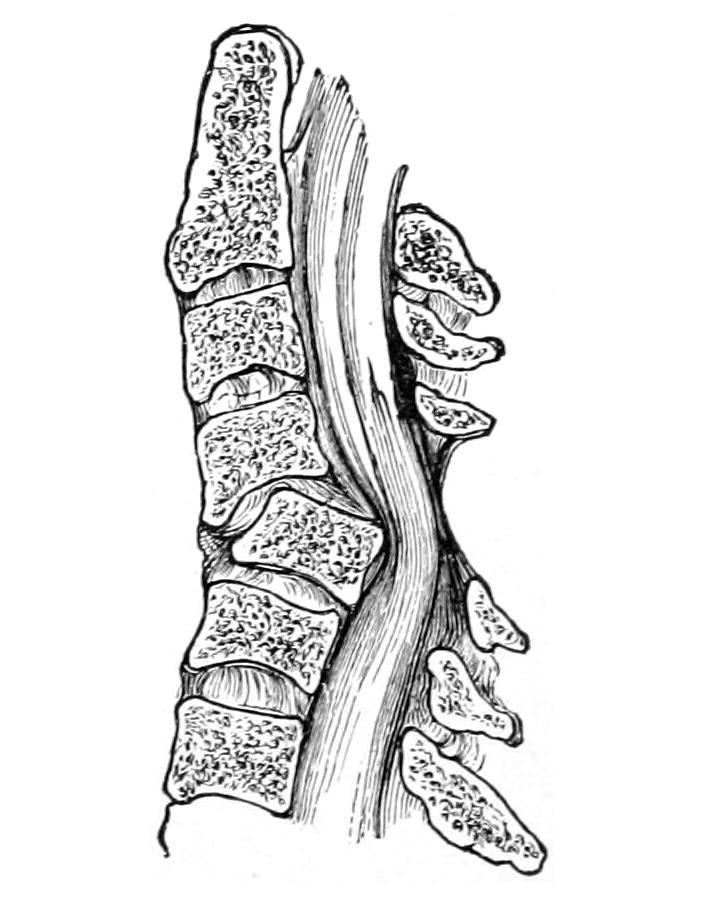

THE SPINE, THE SPINAL CORD AND THE PERIPHERAL NERVES 621